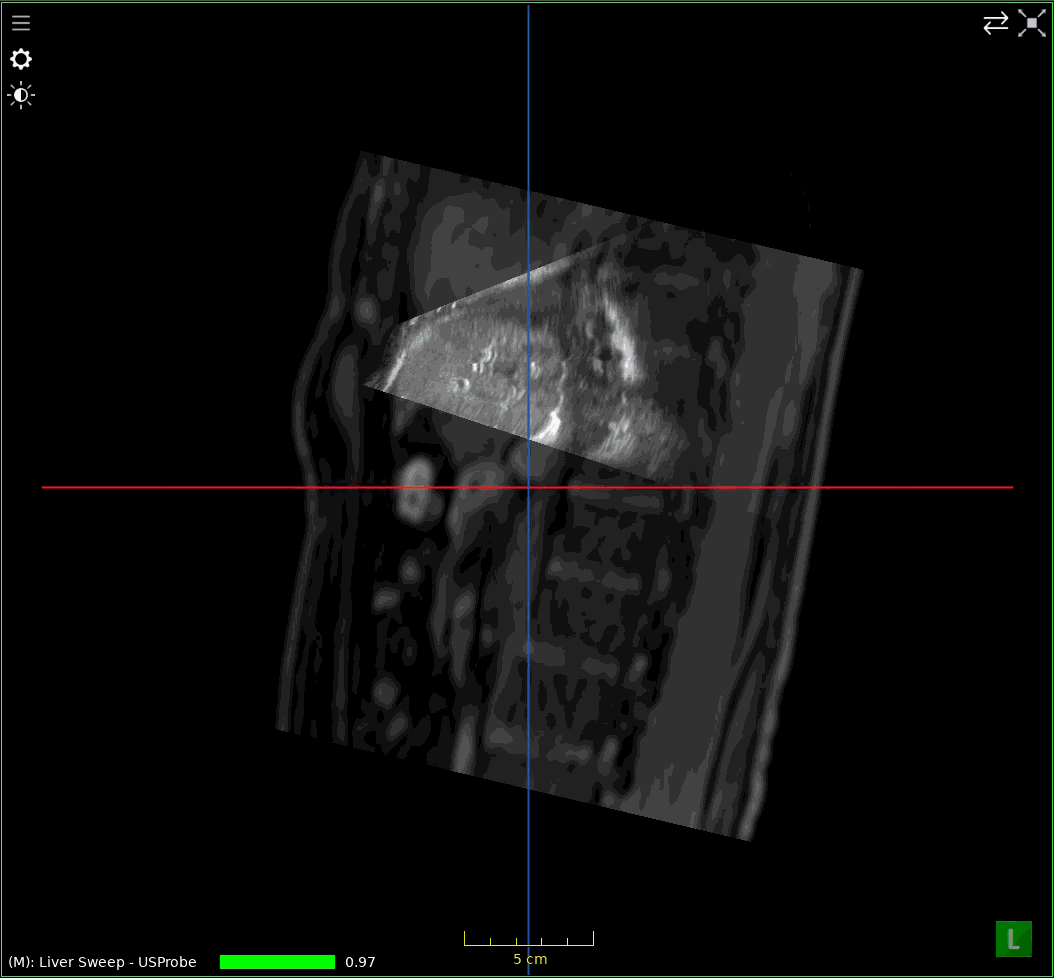

When analyzing registrations of ultrasound sweeps, it is beneficial to link the MPR views to the sweep pose by clicking the Link MPRs button (1).

../../_images/US.UltrasoundRegistrationTutorial.analysis01.png

Link MPR views to sweep pose.